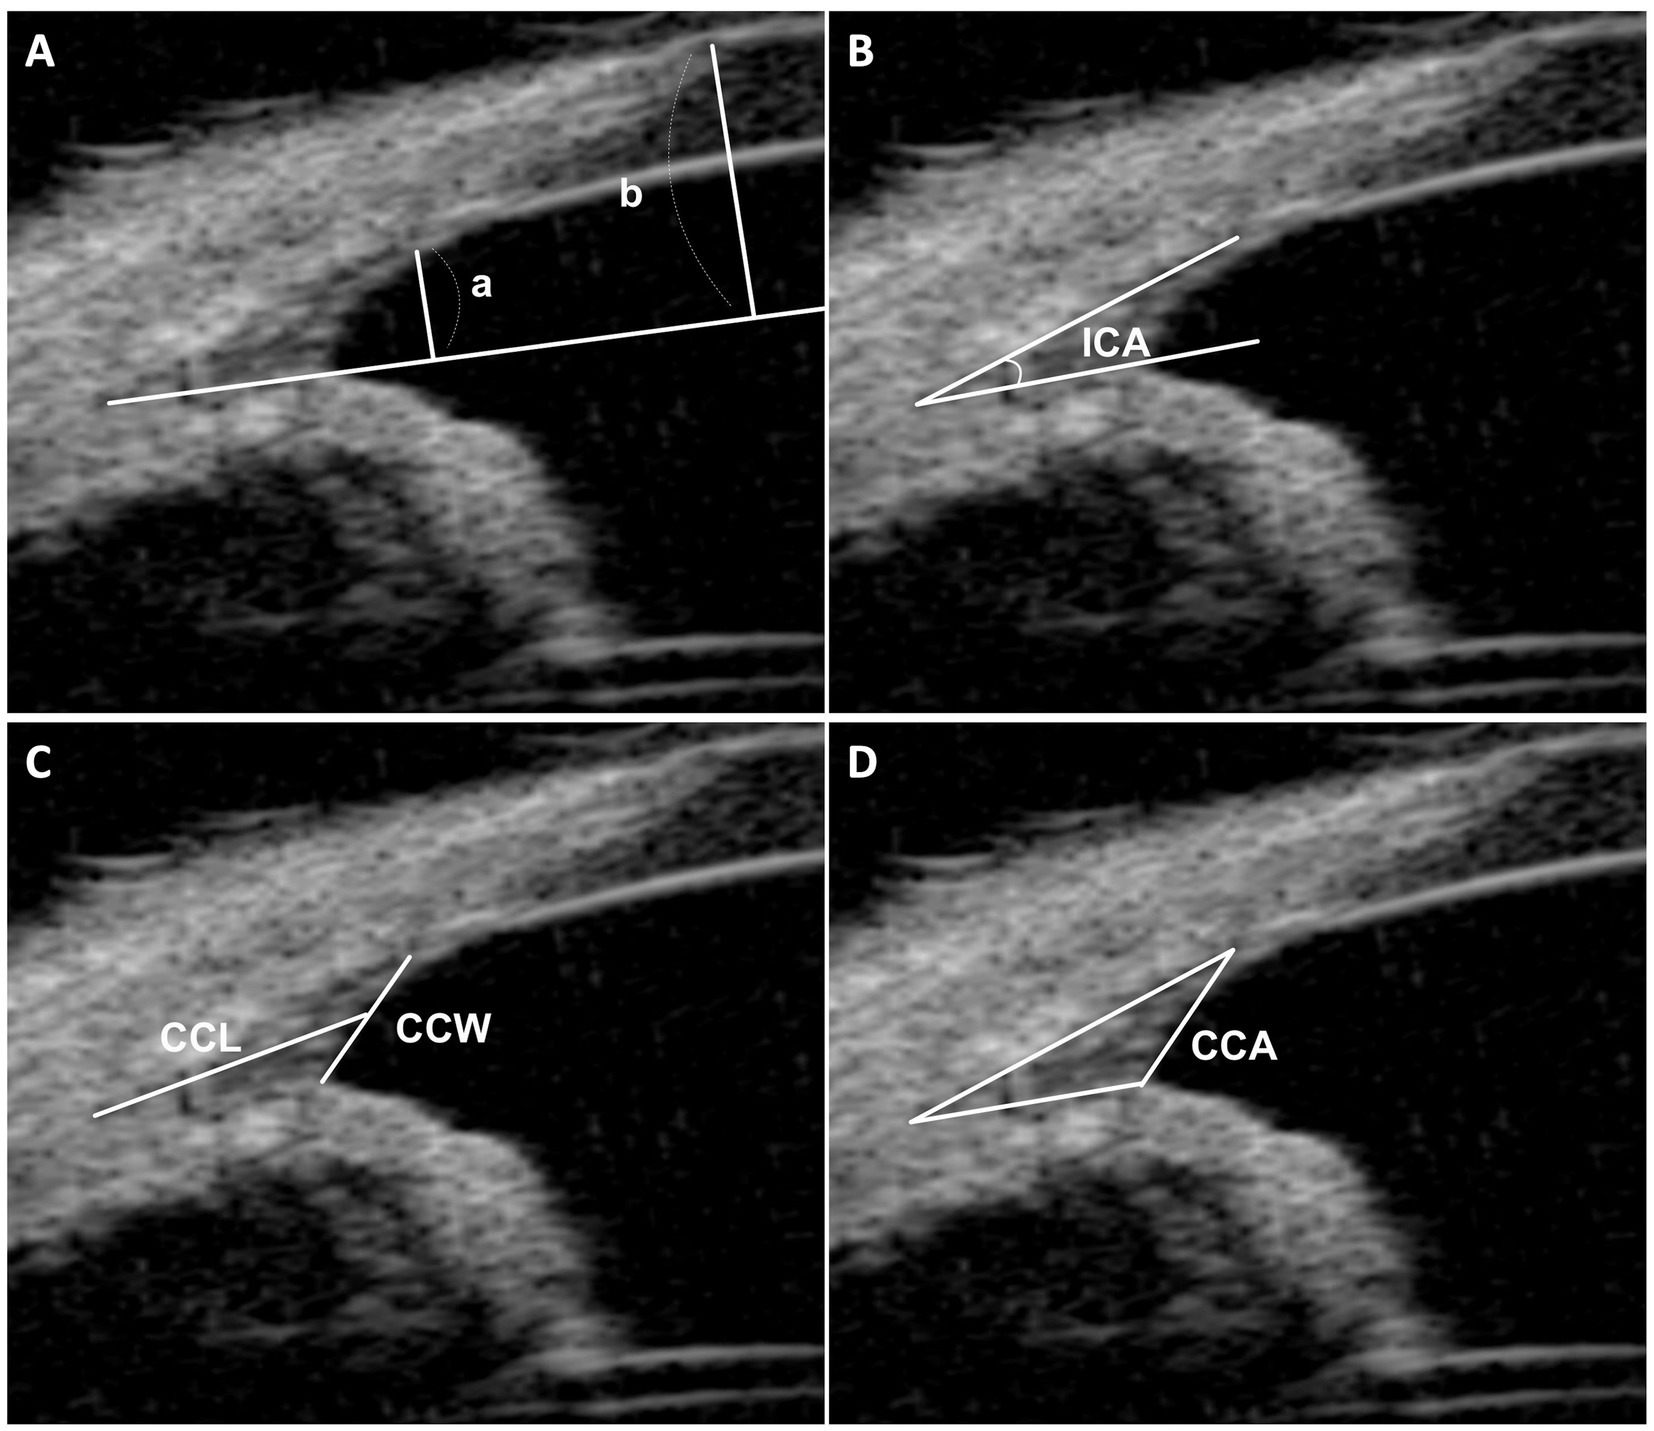

Materiales y métodos: Se analizaron los datos clínicos de 31 ojos de 17 perros en el Hospital Docente Veterinario de la Universidad Nacional de Chungbuk, Corea. La RO-ICA se clasificó como «Ligeramente estrecha», «Estrecha», «Abierta» y «Muy abierta», con los ojos agrupados en «Estrechos» (incluyendo Ligeramente Estrechos y Estrechos) y «Abiertos» (incluyendo Abiertos y Muy Abiertos) para el análisis. Se emplearon métodos estadísticos, incluyendo regresión lineal y comparaciones promedio entre grupos, para explorar las correlaciones entre RO-ICA y parámetros como ICA, ancho CC (CCW), longitud CC (CCL) y área CC (CCA).

Resultados: La distribución mostró «Estrecho» (3 ojos, 9,7%), «Ligeramente Estrecho» (13 ojos, 41,9%) y «Abierto» (14 ojos, 45,2%) como las categorías predominantes. En el grupo abierto, el CCL y el CCA fueron significativamente mayores en comparación con el grupo estrecho. Se observó una correlación positiva entre RO-ICA y CCL, y CCA en todos los grupos. En particular, en el grupo Narrow, RO-ICA demostró una correlación positiva particularmente significativa con todos los parámetros evaluados, incluidos ICA, CCW, CCL y CCA. Sin embargo, no se observó correlación significativa entre el RO-ICA y los parámetros evaluados en el grupo Open. En conclusión, mientras que un RO-ICA más pequeño generalmente se correlaciona con un CC más pequeño, un RO-ICA más grande no garantiza un CC más grande.